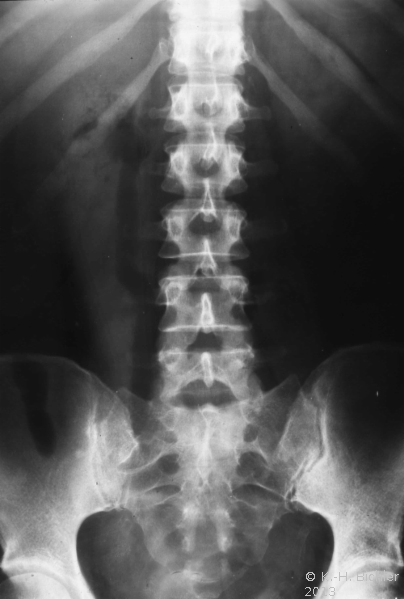

Akute nekrotisierende E. coli-Infektion. Dabei kommt es durch die Glukose spaltenden Bakterien zur Gasentwicklung im Nierenparenchym. Bei den Patienten liegt häufig ein Diabetes vor

Literatur:Schainuck, L. I. et al: "Emphysematous Pyelonephritis", Amer J Urol, 44, 134-139, 1968. Diese Form der Pyelonephritis kommt auch im Kindes- und Jugendalter vor. Das Krankheitsbild ist gekennzeichnet von Bauchschmerzen und Fieber. Die Erkrankung tritt akut mit Zeichen der Allgemeininfektion auf. Im Ausscheidungsurogramm findet sich eine Gasfüllung der ableitenden Harnwege (Abbildung 14).

Die Infektion verläuft destruktiv und prognostisch ungünstig. Bei Nichtansprechen der Therapie ist die Nephrektomie unverzichtbar.